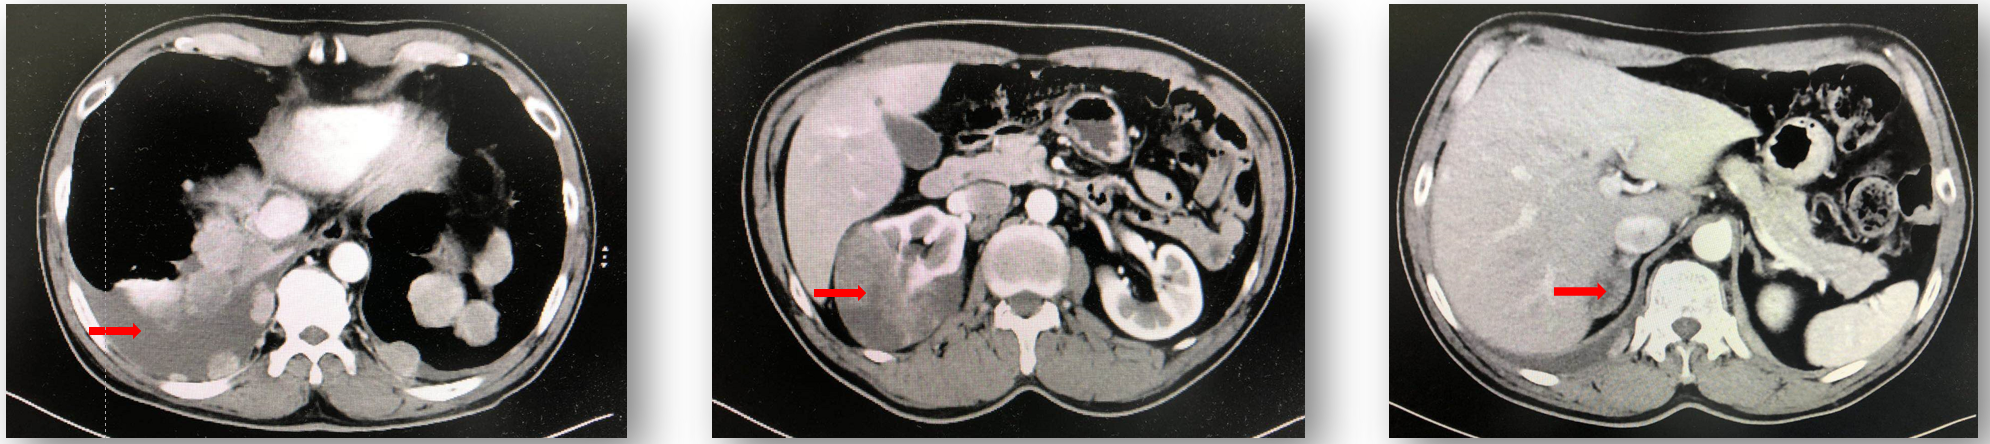

• CT:右肾肿物约70x83mm,考虑肾细胞癌;双肾上腺转移;腔静脉后淋巴结多发转移;双侧胸膜多发转移并双侧胸腔积液。

肾细胞癌, 临床 Ⅳ 期, cT3N1M1。

2017.10行减瘤右肾切除+腹膜后淋巴结清扫

术后病理:透明G3(80%)、管状囊性混合肾细胞癌 (20%) , pT3aN1M1;

一线培唑帕尼(赛贝欣, 800mg QD ): 部分缓解(PR)

一线TKI 13个月:肿瘤进展